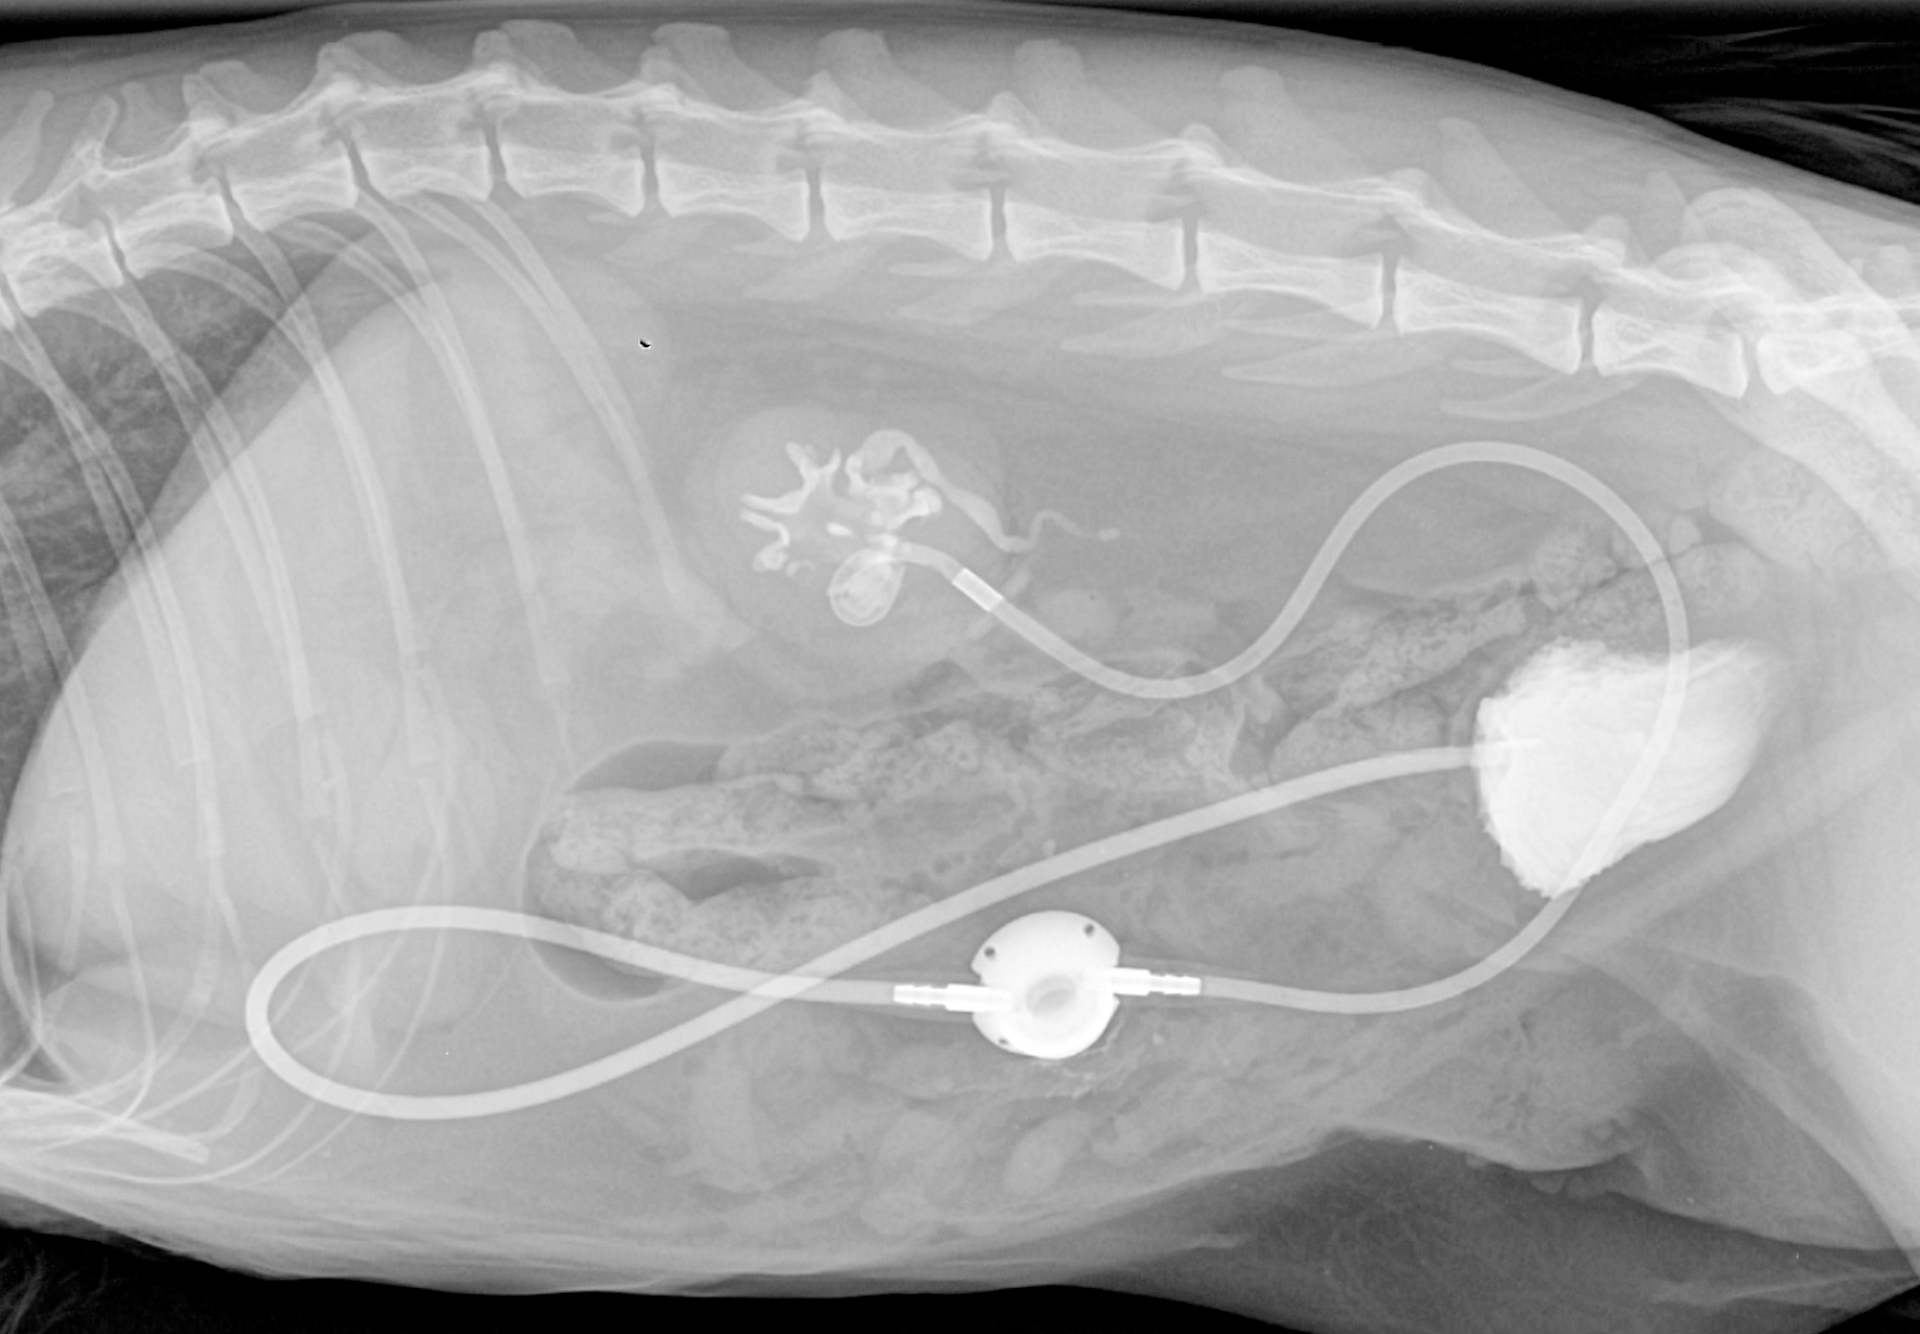

Obstruction urétérale chez un chat Sacré de birmanie de 8 ans

Hutch, chat Sacré de Birmanie de 8 ans, a été présenté en consultation pour abattement et vomissements depuis quelques jours.

A l'échographie abdominale, une dilatation de la cavité pyélique rénale gauche est mise en évidence, avec présence de calculs obstructifs dans l'uretère gauche.

Une pose de SUB a été effectuée, reliant la cavité pyélique gauche à la vessie, en court-circuitant l'uretère obstrué.